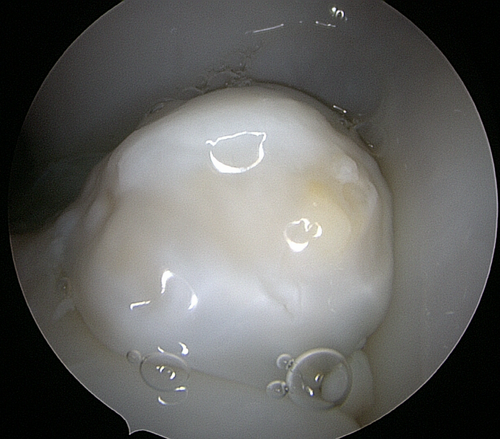

Arthoskopie/ Gelenkspiegelung: Die Spiegelung eines Gelenks durch eine Kamera ermöglicht dessen gründliche Untersuchung und Behandlung. Es gibt verschiedene Erkrankungen, bei denen eine Arthroskopie notwendig ist. Dazu gehören die Entfernung von verknöcherten Knorpelstückchen (Chips) bei der Osteochondrosis Dissecans (OCD) und das Abtragen aufgelockerter Knorpelteile oder angerissener Fasern, wenn diese die Bewegung des Gelenkes stören und Schmerzen verursachen. Das Gelenk wird von diesen „Störfaktoren“ gereinigt und gespült. Während der Arthroskopie kann auch eine zusätzliche direkte Behandlung mit Laser direkt in das Gelenk oder in eine Sehne/ ein Band stattfinden. Darüber hinaus ist die Verwendung von Bluteigentherapien (z.B. PRP) am Meniskus oder den Bändern möglich. Um den Knorpelaufbau zu fördern wird das sogenannte Micropicking oder Microdrilling durchgeführt oder mittels körpereigenen Knochenmarkes und Fibrinkleber die Gelenkfläche unterstützt.